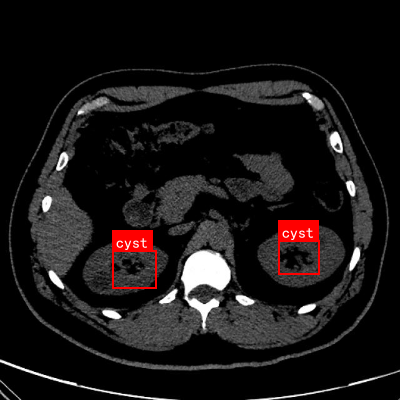

1.4.3. 典型案例分析

上图展示了几个典型病例的检测结果。第一行展示了囊肿的检测结果,模型能够准确识别囊肿的位置并生成精确的分割掩膜;第二行展示了肾脏区域的分割结果,模型能够完整勾勒出肾脏的轮廓;第三行展示了结石的检测结果,虽然结石尺寸较小,但模型仍然能够准确定位;第四行展示了肿瘤的检测结果,模型能够区分肿瘤与周围正常组织。

这些案例表明,我们的方法在实际临床应用中具有很高的实用价值,能够辅助医生快速准确地识别和定位肾衰竭病变,提高诊断效率和准确性。👨⚕️